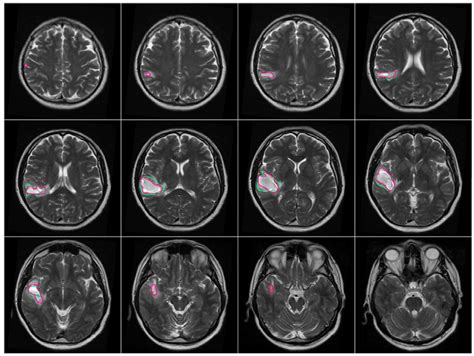

• Brain tumors: To determine the size, location, and boundaries of a tumor, as well as how it responds to treatment.

• Multiple Sclerosis (MS): To detect active plaques or lesions caused by the disease.

• Vascular abnormalities: Including aneurysms or arteriovenous malformations, to better visualize blood flow.

• mri brain with contrast images